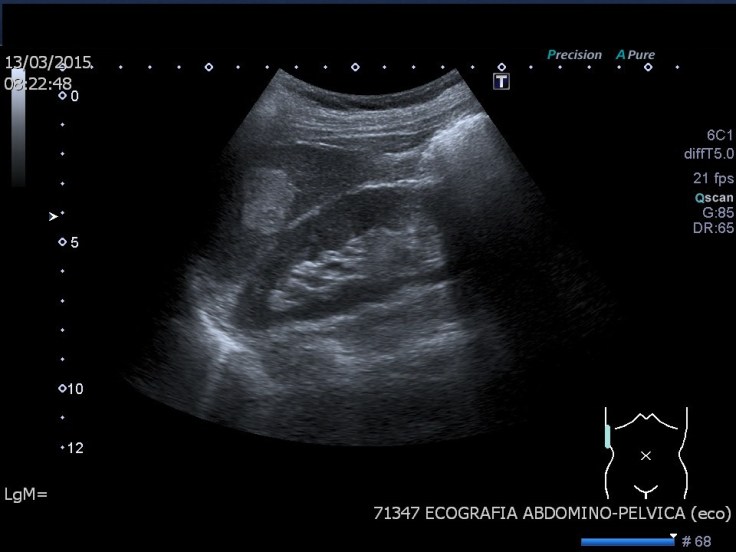

La imagen es un corte sagital realizada con sonda convex de baja frecuencia, estamos usando 6 mHz con armónicos, ganancia general de 86 y un rango dinámico de 65, es decir un valor medio. El pictograma indica la posición en decúbito supino y corte sagital.El preset es de ecografía de Abdomen General.La profundidad de estudio es de 12 cms. El foco está situado en torno a los 6 cms.

Anatómicamente tenemos una imagen donde observamos la relación hepatorrenal, donde ambos órganos son isoecogénicos.Entre ambos existe una línea de separación fina e hiperecogénica, corresponde al Espacio de Morrison, lugar de depósito de líquido ascítico habitual.

En el Hígado llama la atención una estructura hiperecogénica y homogénea, ligéramente redondeada,en el plano anteroposterior mide en torno a 2,5 cms y corresponde con un hemangioma típico.

El Riñón es de un aspecto normal, la corteza en hipoecogénica, el seno renal, hiperecogénico, no está dilatado, mide algo más de 9 cms, su ecoarquitectura es correcta, no tiene ni masas ni imágenes que sugieran litiasis.

Riñón derecho e hígado comparten una región en la imagen, es la que corresponde al polo superior del riñón y a la porción más caudal y externa del hígado, es la zona de la Suprarrenal derecha, lugar que debemos encontrar libre a partir del año de vida, es decir, no debemos ver dicha suprarrenal ni tampoco ninguna LOE a ese nivel.

A nivel del polo inferior del Riñón, superficial, observamos una imagen hiperecogénica, curva, con una llamativa sombra acústica posterior que corresponde con gas intestinal correspondiente a la tercera porción del duodeno, el gas es el culpable de esta ausencia de información que se traduce en un artefacto típico del gas intestinal.

La flecha negra está marcando el Músculo Psoas, que «acuna» al riñón derecho.